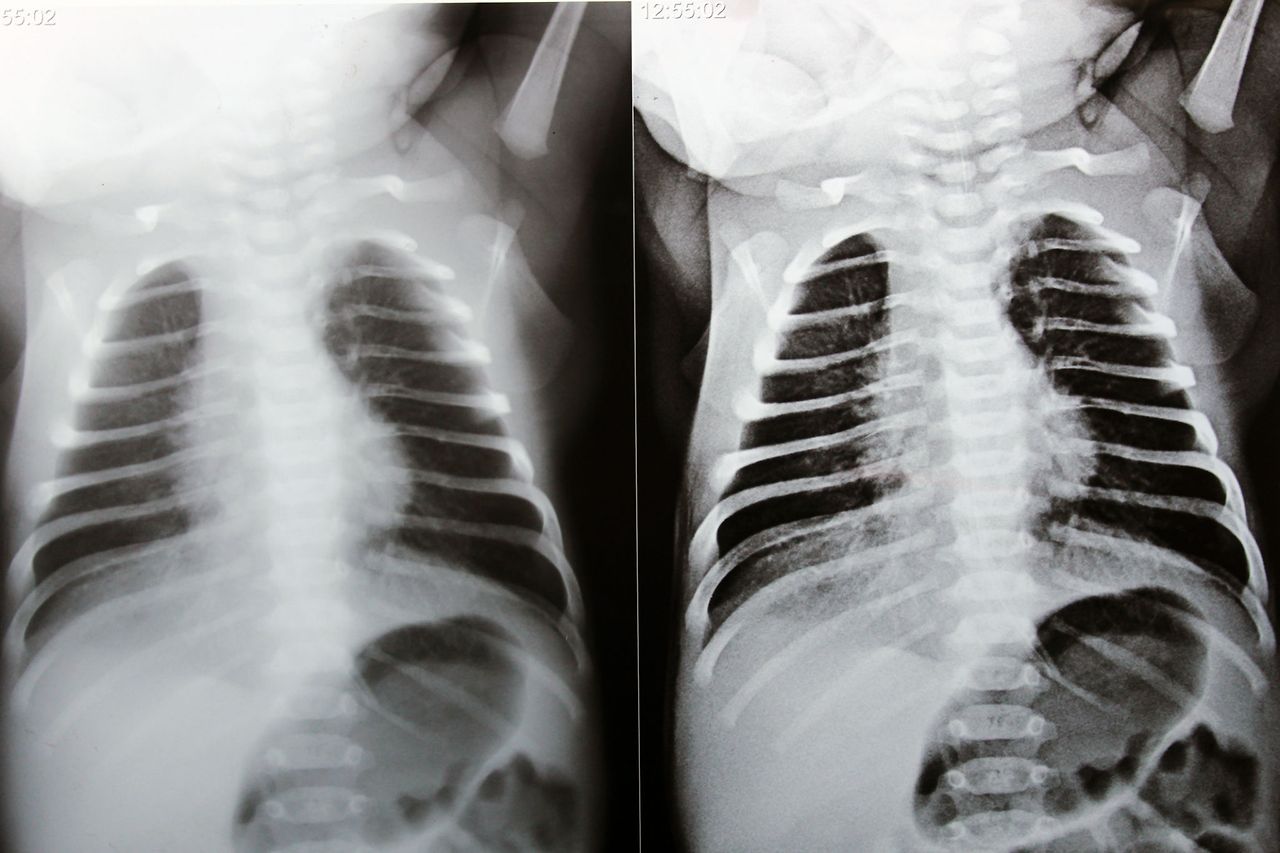

① 신생아 기흉 (Pneumothorax)

폐 안에 있어야 할 공기가 바깥으로 새어나가

폐와 흉벽 사이 공간에 공기가 차면서

폐가 바깥에서 눌려 접힌 상태를 말합니다.

② 신생아 무기폐 (Atelectasis)

폐포 안에 공기가 충분히 차지 않아

일부 폐가 제대로 펴지지 못한 상태를 의미합니다.